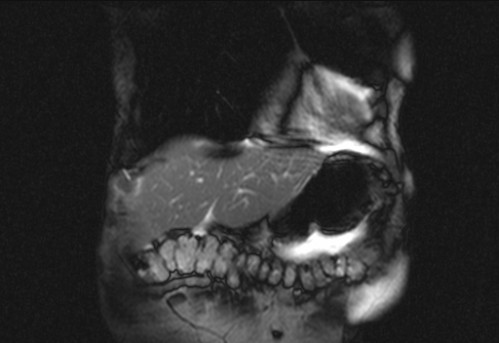

Auffälliges Abdomen bei der Vorsorgeuntersuchung einer älteren Dame

ICD: C64

68 Jahre alte Frau. Sie geht zur Darmspiegelung im Rahmen ihrer Krebsvorsorgeuntersuchung. Der Internist bemerkt bei der ergänzenden sonografischen Untersuchung des Abdomens einen auffälligen Befund.